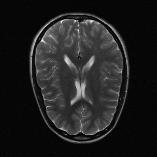

Recently, deep neural networks have greatly advanced undersampled Magnetic Resonance Image (MRI) reconstruction, wherein most studies follow the one-anatomy-one-network fashion, i.e., each expert network is trained and evaluated for a specific anatomy. Apart from inefficiency in training multiple independent models, such convention ignores the shared de-aliasing knowledge across various anatomies which can benefit each other. To explore the shared knowledge, one naive way is to combine all the data from various anatomies to train an all-round network. Unfortunately, despite the existence of the shared de-aliasing knowledge, we reveal that the exclusive knowledge across different anatomies can deteriorate specific reconstruction targets, yielding overall performance degradation. Observing this, in this study, we present a novel deep MRI reconstruction framework with both anatomy-shared and anatomy-specific parameterized learners, aiming to "seek common ground while reserving differences" across different anatomies.Particularly, the primary anatomy-shared learners are exposed to different anatomies to model flourishing shared knowledge, while the efficient anatomy-specific learners are trained with their target anatomy for exclusive knowledge. Four different implementations of anatomy-specific learners are presented and explored on the top of our framework in two MRI reconstruction networks. Comprehensive experiments on brain, knee and cardiac MRI datasets demonstrate that three of these learners are able to enhance reconstruction performance via multiple anatomy collaborative learning.